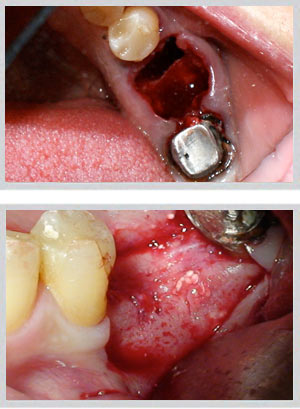

Upper jaw: GBR (guided bone regeneration) for moderate buccal defects; block bone grafting for larger volume requirements. Socket preservation at time of extraction prevents bone loss from occurring in the first place.

Lower jaw: Block bone grafting for severe buccal wall defects. Easy Graft Crystal (non-resorbable beta-tricalcium phosphate) for minor to moderate deficiencies. Socket preservation equally critical.

Dr. Zarifeh's preferred protocol combines synthetic Easy Graft with autogenous bone chips — pairing the structural scaffold of a synthetic material with the biological activity of the patient's own cells. The selection is made individually per case based on defect size, location, and planned implant timeline.